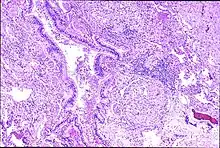

| Peribronchal non-necrotizing granuloma from berylliosis | |

Granuloma formation is seen in other diseases such as tuberculosis and sarcoidosis. Sarcoidosis, like berylliosis, also produces granulomas without a necrotic core, and so distinction between the two processes can be difficult.

In susceptible persons, beryllium exposure can lead to a cell-mediated immune response. The T-cells become sensitized to beryllium. Each subsequent exposure leads to an immune response involving CD4+ helper T-lymphocytes and macrophages accumulating in the lungs. As this response continues macrophages, CD4+ T-lymphocytes and plasma cells aggregate together to form the noncaseating granulomas.[6][7] When beryllium is phagocytized by macrophages, the beryllium triggers macrophage apoptosis, thereby reducing beryllium clearance from the lungs and eventually resulting in secondary necrosis and lysis.[8] Eventually, the outcome is fibrosis of the lung.[9][10]